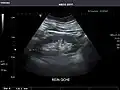

Left kidney -

Kidneys: Right and left kidneys measure 11.5 cm and 12 cm in length respectively. No hydronephrosis. Small left lower pole kidney cyst.